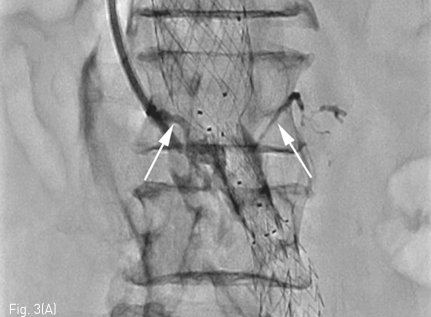

초음파 유도 하에 우측 내경정맥을 천자하여 Rosch-Uchida transjugular liver access set (Cook, Bloomington, IN, USA) 에 포함된 10F sheath 를 하대정맥에 삽입한 뒤 sheath tip 은 제3 요추의 상연에 위치시켰음. 이후 set 에 포함된 14G stiffening cannula에 Rosch-Uchida needle 을 삽입하고 투시의 전후 및 측면 영상을 이용하여 needle의 위치와 천자방향을 확인한 뒤 하대정맥에서 대동맥류를 직접 천자하였음. 이후 needle tip을 동맥류내의 제3-4 요추사이공간 level 의 제3 허리동맥 기시부로 위치시키고 혈관조영술을 시행하였음. 혈관조영술에서 type II endoleak 의 원인이 되는 제3 허리동맥이 관찰되었으며(Fig. 2), 이를 N-butyl cyanoacrylate 와 lipiodol 을 1:2 로 혼합한 용액 4.5mL 를 주입하여 색전술을 시행하였음. 시술 중 시행한 Fluoroscopy 와 시술 후시행한 CT에서 모두 표적인 제3 허리동맥 내부에 lipiodol 이 차 있는 것을 확인한 뒤 시술 종료하였음(Fig. 3)

Fig 3b

Fluoroscopy during the embolization (A) and immediate post-embolization CT (B) shows N-butyl cyanoacrylate and lipiodol mixture fills within the aneurysmal sac and lumbar arteries.